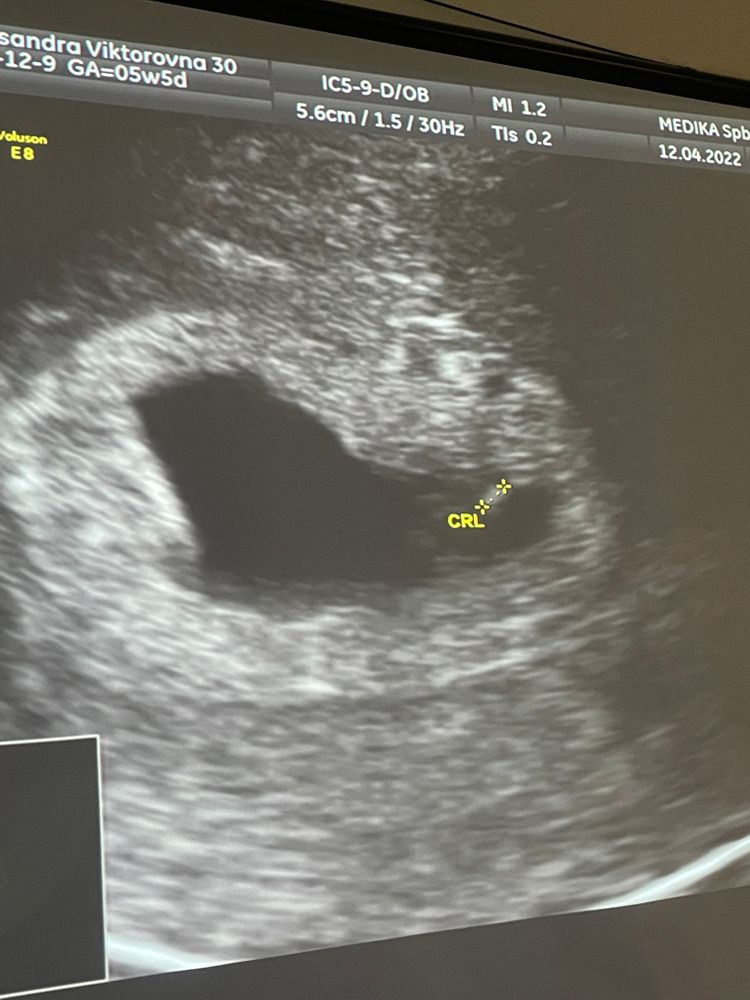

Сердечко послушать не дали, но я видела как внутри меня двигается что то очень крохотное 💗☺️ дай Бог, каждой таких эмоций , которые я испытала сегодня 🤍